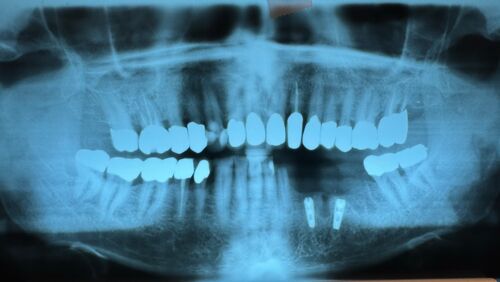

Neuer Kieler Patient erhält zwei Implantate

10249

In regio 33 und 35, mit distaler Abwinkelung zwei Mplantate inseriert.

Durch das bewusst schräge Inserieren des Implantat 36 kommt die klinische Krone in regio 36 durch die schleimhaut hinduch. Die Implantate sitzen aber beide in möglichst gesundem Eigenknochen, statt das Implantat 36 in vorgeschädigten Knochen zu setzen, der erst mit einem neu zu bildenden Knochen hätte neu aufgebaut werden müssen.

Wenn man einen Bleistift in der Achse des hinteren Implantates anlegt, sieht man, dass der Implantataufbau, der das Zahnfleisch durchbricht, dann tatsächlich dort klinisch im Mund aus dem Zahnfleisch rauskommt, wo vohrer die natürliche klinische Zahnkrone saß. Dazu nutzt man dann einen geinkelten Impülantataufbau und "Fertig ist die Laube!"